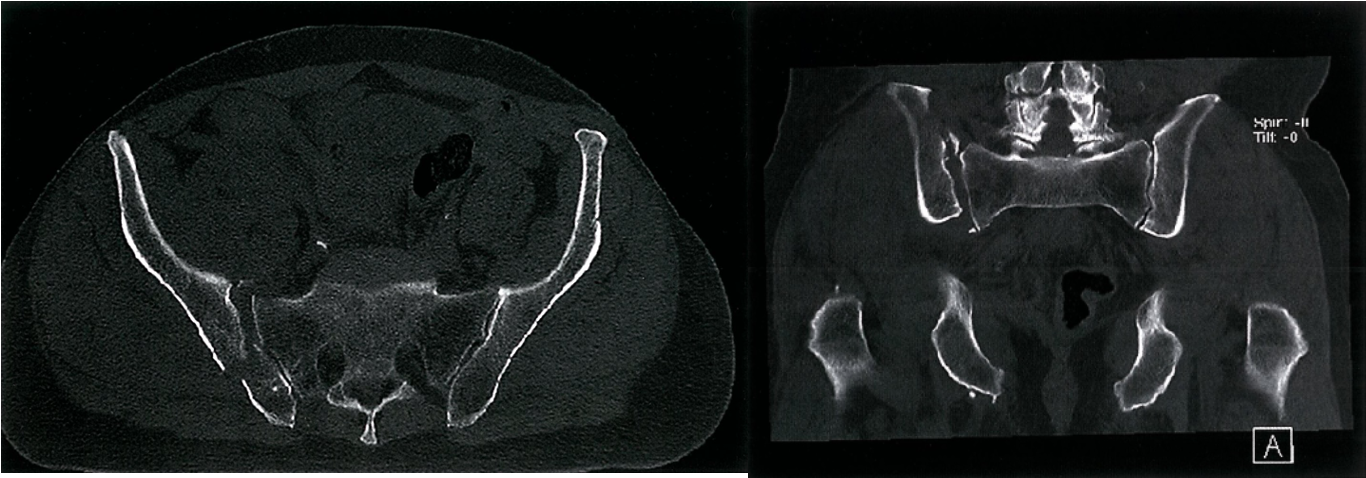

A. Posterior pelvic ring fracture - CT pelvis (bone window; axial) There is disruption of the right sacroiliac joint with a fracture demonstrated through the right ilium.

B. Post. pelvic ring fracture - CT pelvis (bone window; coronal) There is widening of the right sacroiliac joint with a small fracture fragment demonstrated at the superior aspect of the joint